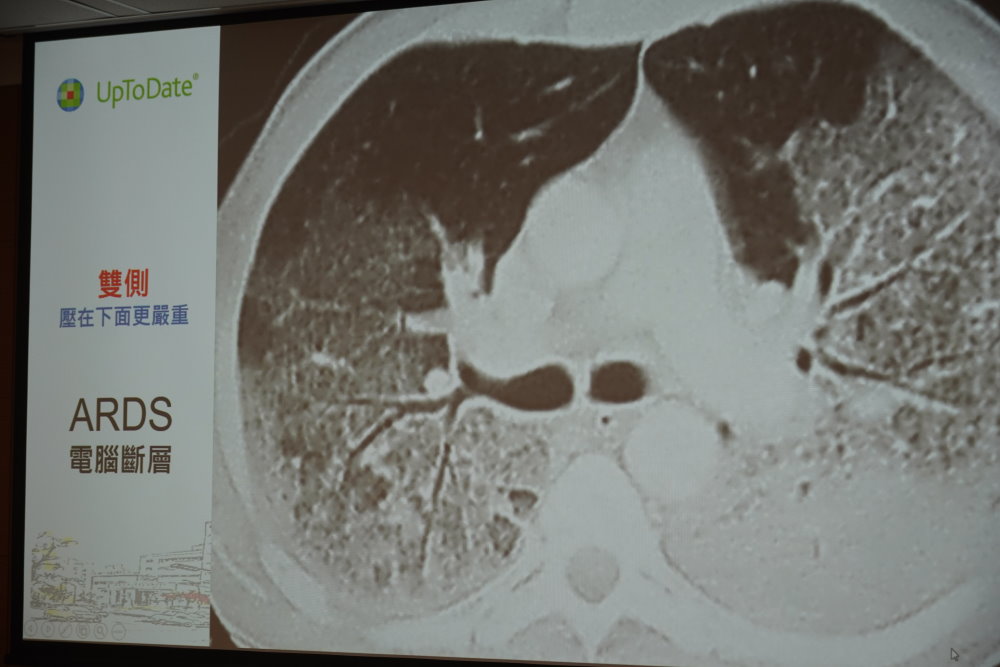

ARDS的診斷標準主要為胸部影像學(X光或電腦斷層)和柏林定義 (Berlin Definition) 。影像學通常顯示雙側瀰漫性的肺浸潤,也有人稱為「大白肺」。柏林定義則包括急性發病時間為7天內,並根據氧合指數 (PaO2/FiO2) 將疾病嚴重程度分成輕微 (200-300)、中度 (100-200)與重度 (<100)。